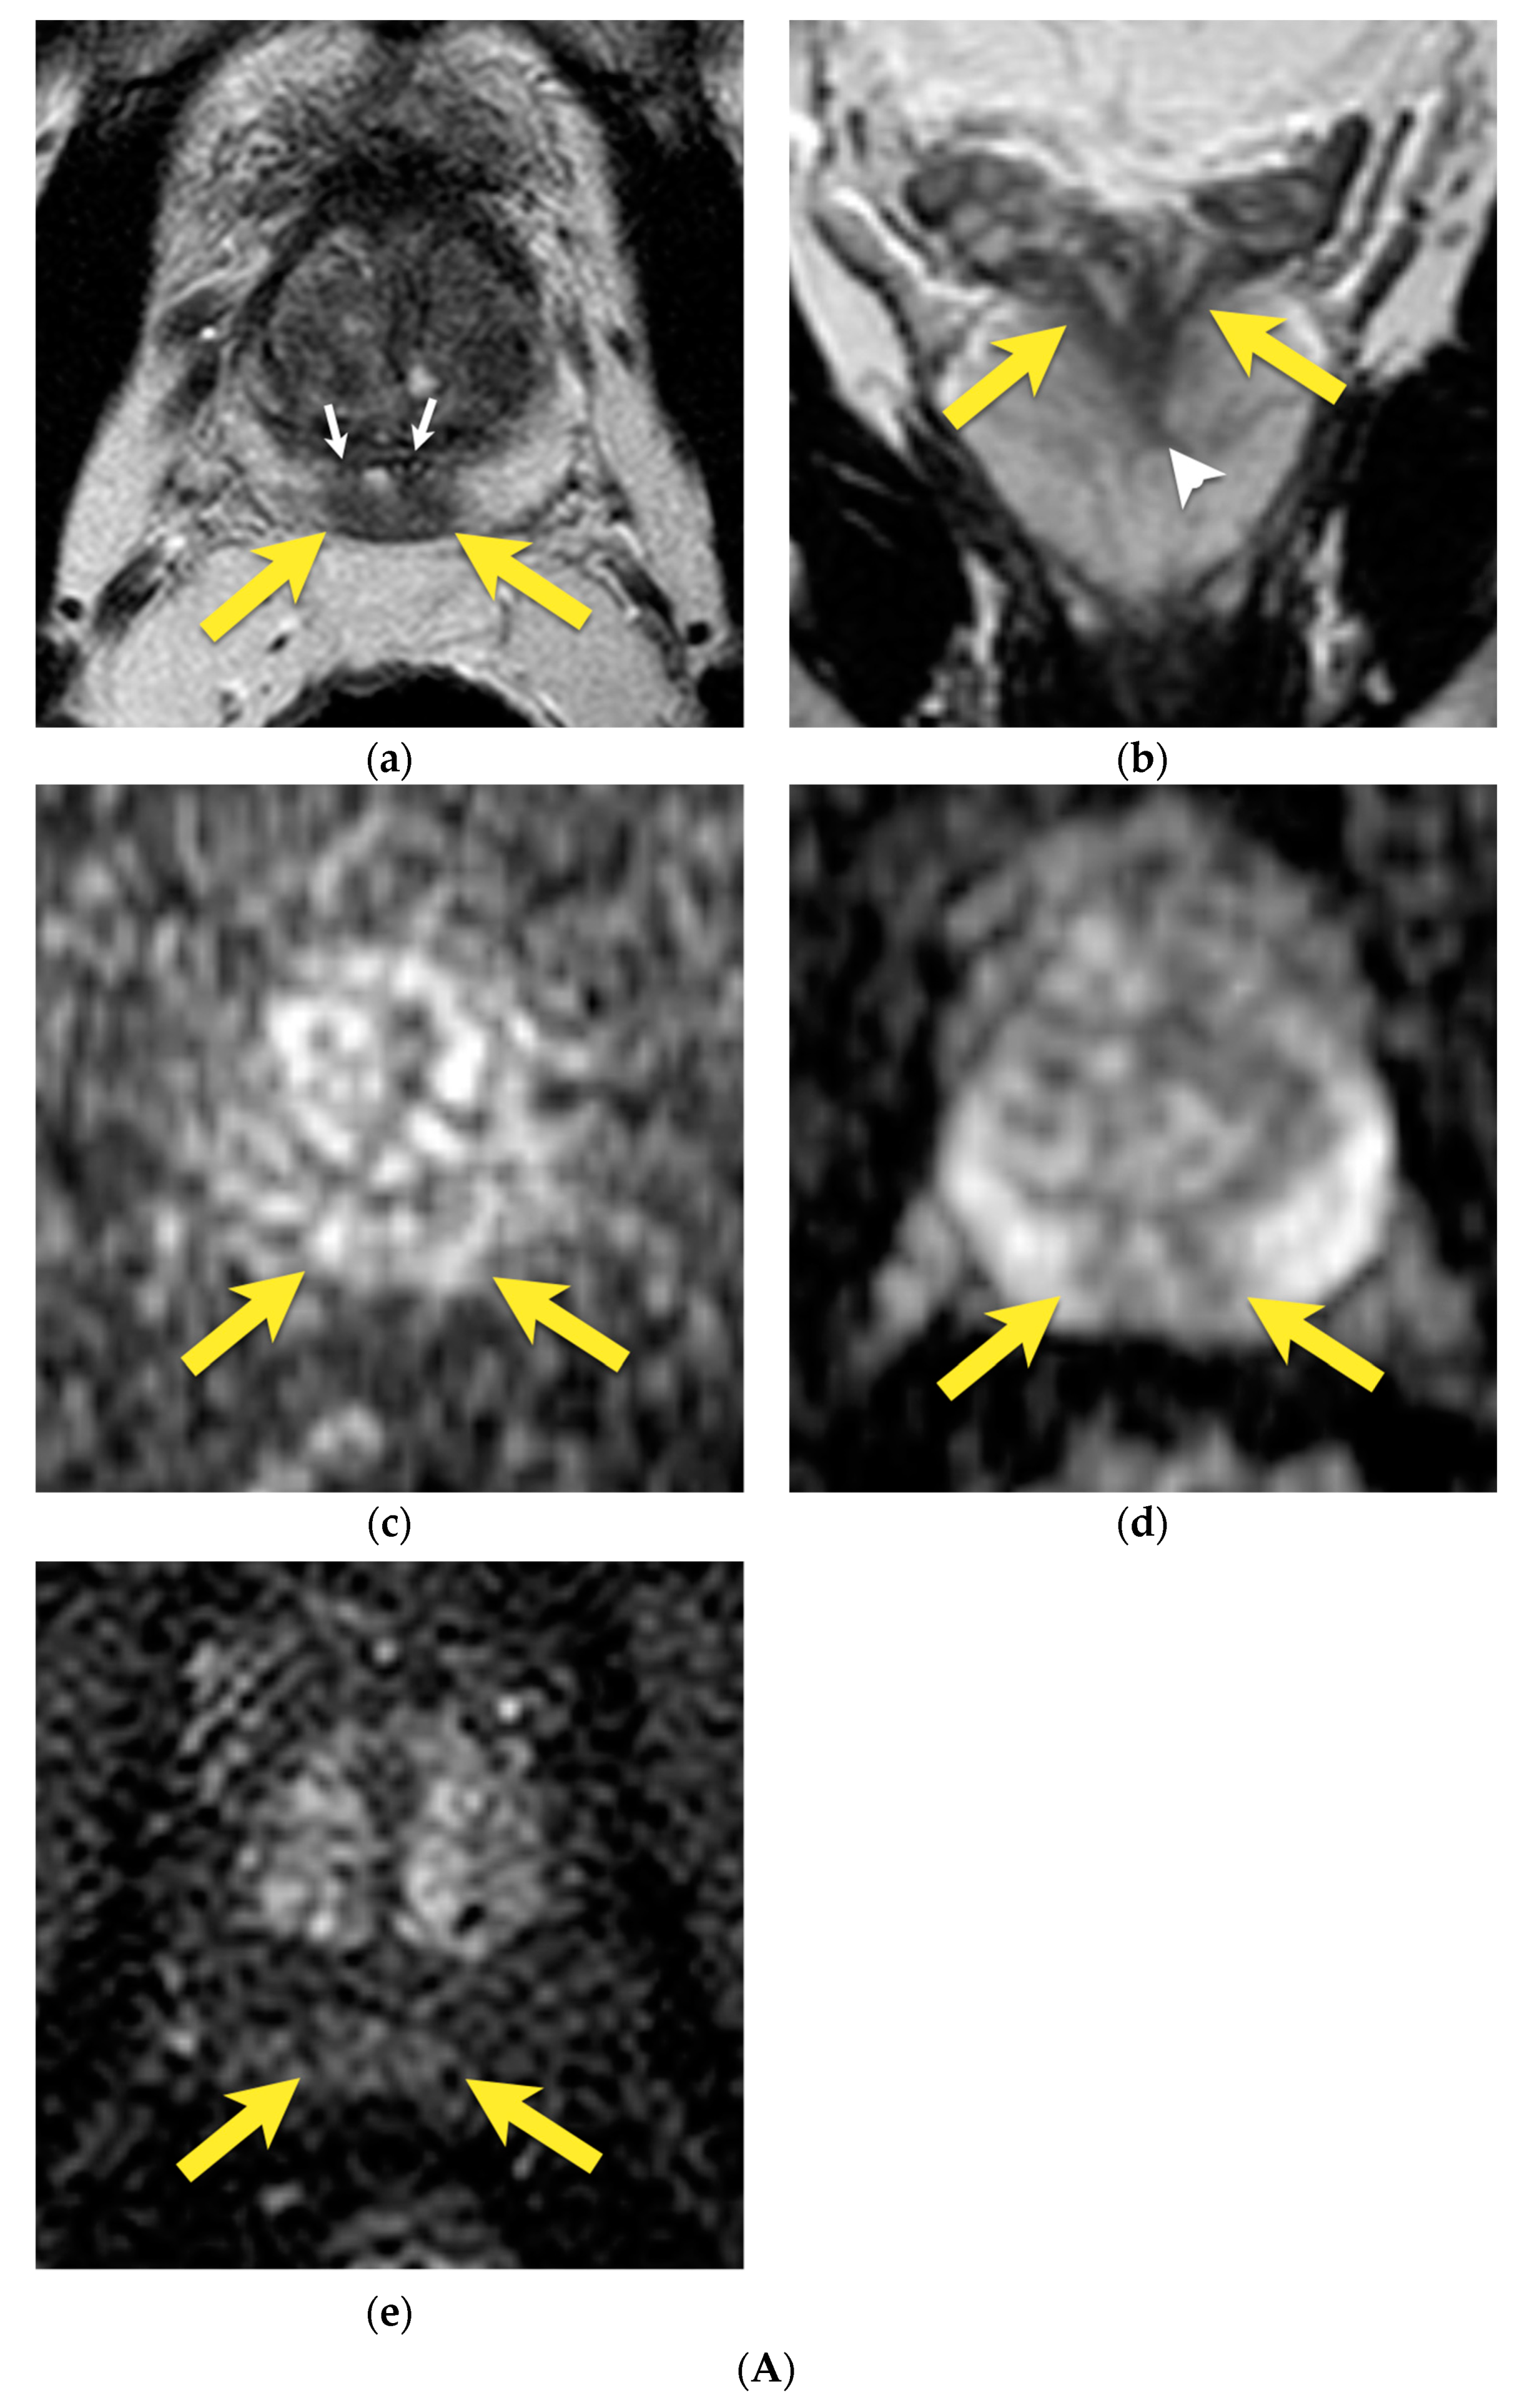

11. Quality of Images